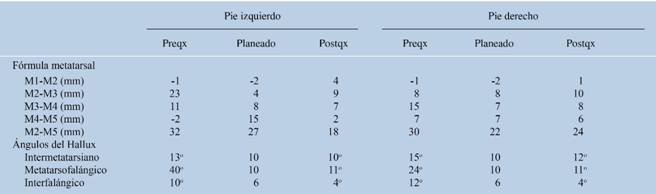

Se lleva a cabo planeación quirúrgica en proyecciones radiográficas dorsoplantar y lateral según se indica en la Tabla 2 con la finalidad de tratar el antepié como unidad funcional.